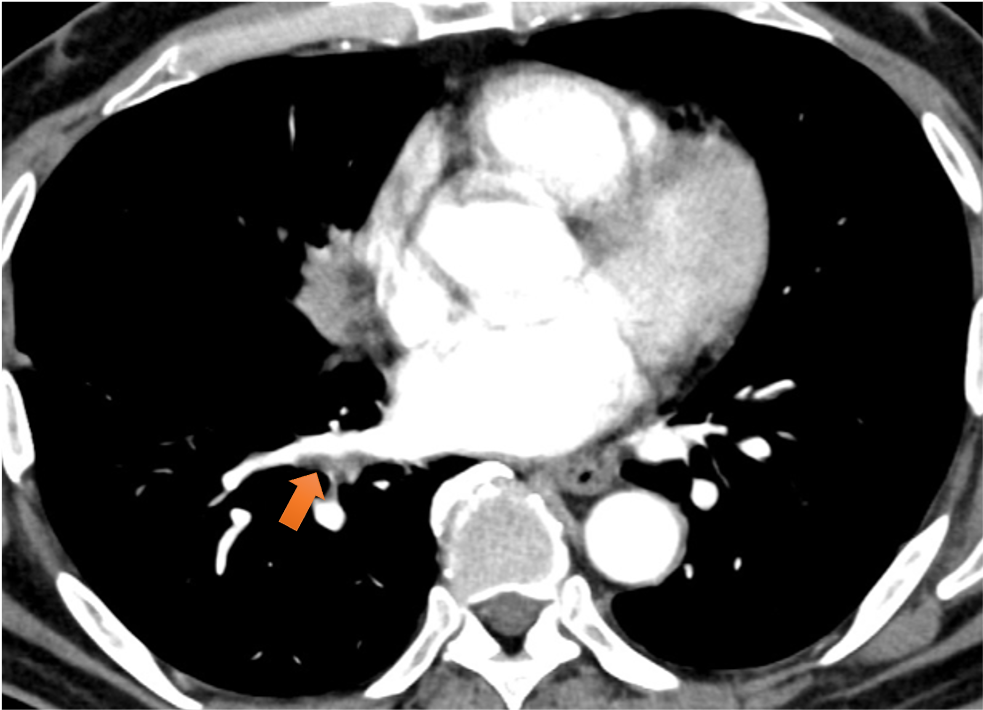

図6.肺動脈造影欠損像

右肺下葉動脈(A8)、左肺上下葉動脈(A3やA8、A9など)に造影欠損あり、造影で一部、増強効果を伴っており、腫瘍塞栓/血栓が疑われた。

図7.肺静脈造影欠損像

右下葉肺静脈壁に沿うように造影欠損あり、腫瘍進展が疑われた。化学療法後、消失が確認された。